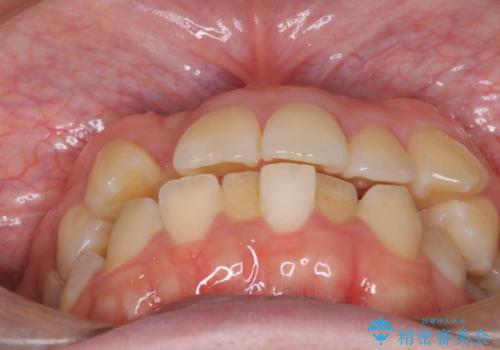

- 患者様は、結婚式までに歯並びを整えたいとのご要望で来院されました。診断の結果、上下左右の第一小臼歯を抜歯し、歯列全体を整える計画としました。審美性を重視し、目立ちにくいホワイトワイヤーを使用した矯正を提案しました。治療期間は2年を目安とし、結婚式までに前歯の整列と噛み合わせを優先的に整えるスケジュールで進めました。定期的な調整と経過観察を通じて、計画的に治療を進めました。

結婚式までに仕上げるため、通常よりも細かく調整を行い、歯の動きを効率的に管理しました。審美ワイヤーを使用したことで、治療中も目立ちにくく、写真撮影などの日常生活での見た目の負担を軽減しました。抜歯部分のスペースを閉じる際には、前歯の位置や噛み合わせのバランスに配慮し、過度な力がかからないよう進めました。患者様の大切なイベントに間に合うよう治療計画を立て、理想的な仕上がりを実現しました。